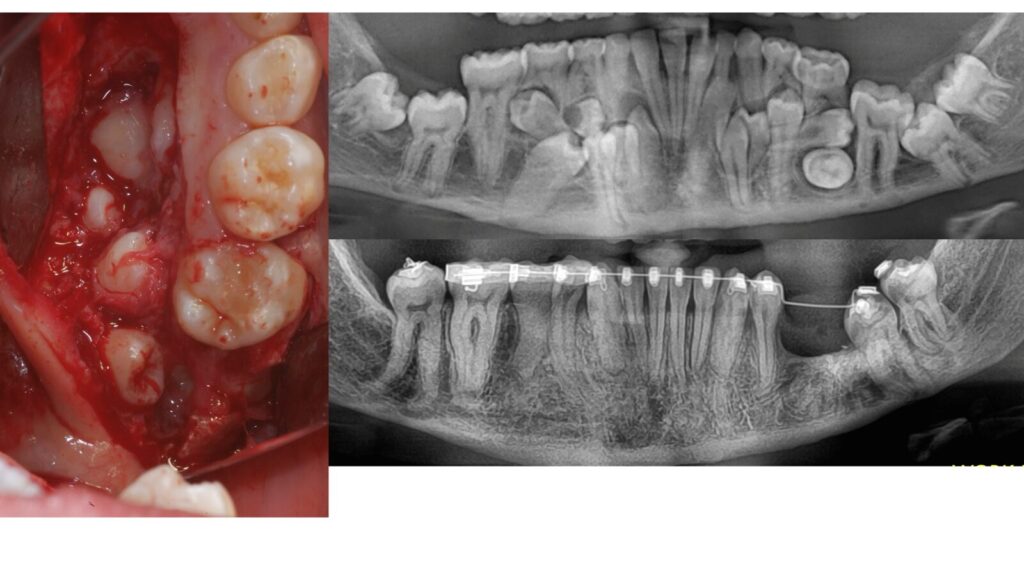

- INDAGINE DIAGNOSTICHE (radiografie indorali,OPT,TC)

- INTERPRETAZIONE PRECHIRURGICA DELLA TC

Dentascan e CBCT (Tac Cone Beam) - TECNICHE ANESTESIOLOGICHE

- VALUTAZIONE DI CASI CLINICI

• VALUTAZIONE DI CASI CLINICI

CORSISTI DI ESTRAZIONI COMPLESSE DI III° MOLARI